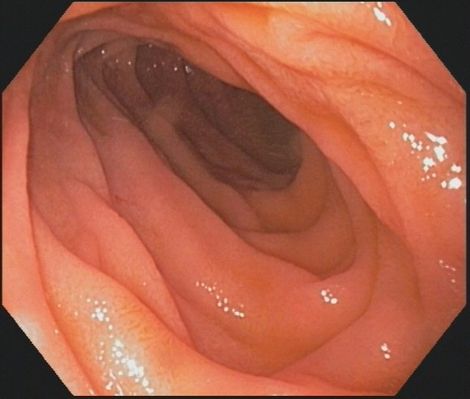

Koloskopie (Darmspiegelung): Die Darmspiegelung ist die effektivste und zuverlässigste Methode, Darmkrebs zu verhindern oder in einem sehr frühen Stadium zu erkennen. Werden Darmpolypen - die Vorstufen von Darmkrebs - während der Koloskopie entdeckt, können sie in den meisten Fällen sofort endoskopisch entfernt werden. Zur Früherkennung von Darmkrebs bezahlen die gesetzlichen Krankenkassen ab dem 56. Lebensjahr regelmäßige Vorsorgekoloskopien. Wenn in der Familie Fälle von Darmkrebs aufgetreten sind oder eine genetische Vorbelastung besteht oder besondere Risikofaktoren vorliegen - etwa eine chronisch-entzündliche Darmerkrankung - werden Vorsorgekoloskopien früher und in kürzeren Abständen durchgeführt.

Bei Änderung der Stuhlgewohnheiten oder Blutungen und bei Verdacht auf eine chronisch entzündliche Darmerkrankung ist die Darmspiegelung die wichtigste Maßnahme, die in ihrer Aussagekraft durch keine andere Methode zu ersetzen ist.

Bei der Darmspiegelung wird ein dünner, biegsamer, Schlauch (das Koloskop), über den After in den Darm eingeführt und vorsichtig bis zum Übergang vom Dünndarm zum Dickdarm geschoben ("Bauhin'sche Klappe"). Dabei wird etwas Luft in den Darm geblasen, damit er sich entfaltet. Dann wird das Endoskop sehr langsam zurückgezogen und die Darmwand genau begutachtet. Von veränderten Schleimhautbereichen werden mit Hilfe einer kleinen Zange Gewebeproben entnommen, Darmpolypen können sofort entfernt werden. In einigen Fällen kann durch Aufbringen von Farbe eine bessere Beurteilbarkeit erreicht werden (Chromoendoskopie).

Sie bekommen in der Regel ein Schlafmittel und spüren von dem Eingriff nichts, die Untersuchung dauert etwa 15 bis 20 Minuten (Sedierung (link)). Während der Untersuchung und im Aufwachraum erfolgt eine Überwachung der Sauerstoffsättigung ("Clip am Finger") und der Herzfrequenz, bei Risikopatienten auch des Blutdrucks. Die Koloskopie ist sehr risikoarm, Komplikationen, wie etwa eine Verletzung der Darmwand oder eine Blutung kommen extrem selten vor. Vor der Untersuchung führen wir mit Ihnen ein ausführliches Gespräch über den Ablauf der Untersuchung und mögliche Risiken.